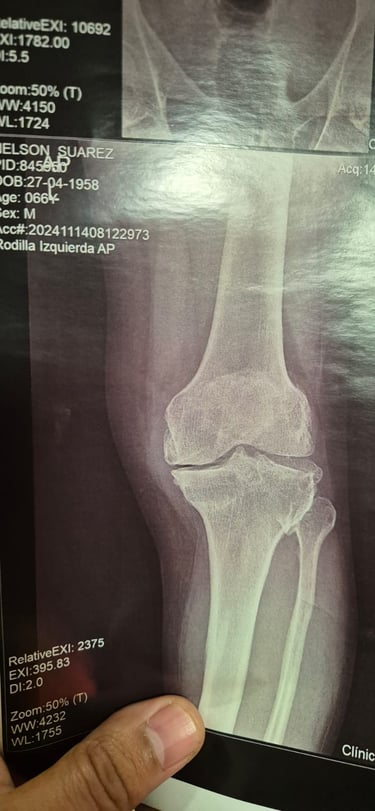

Cirugía de rodilla

Lesiones de meniscos y ligamentos (como LCA en rodilla)